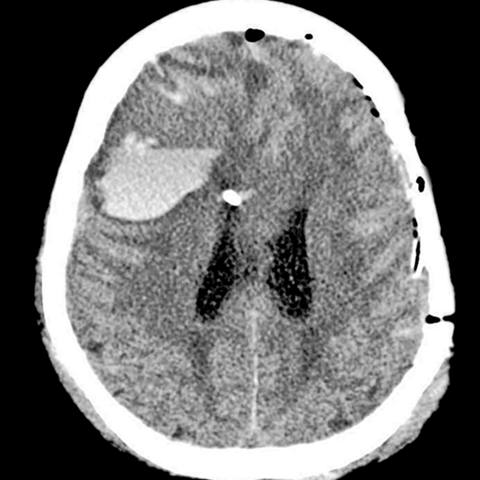

Hematoma